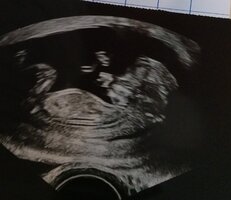

no ainaki raskaanaolevien kanssa henkisistä yhteyksistähä ei vielä tiiä